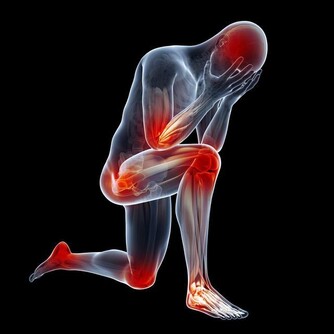

若脂肪主要分佈於臀部,這種梨型肥胖或皮下型肥胖,對中老年人的關節損傷也是一個大問題,不容忽視。因此,中老年人保持健康的體重,對身體健康來說至關重要。